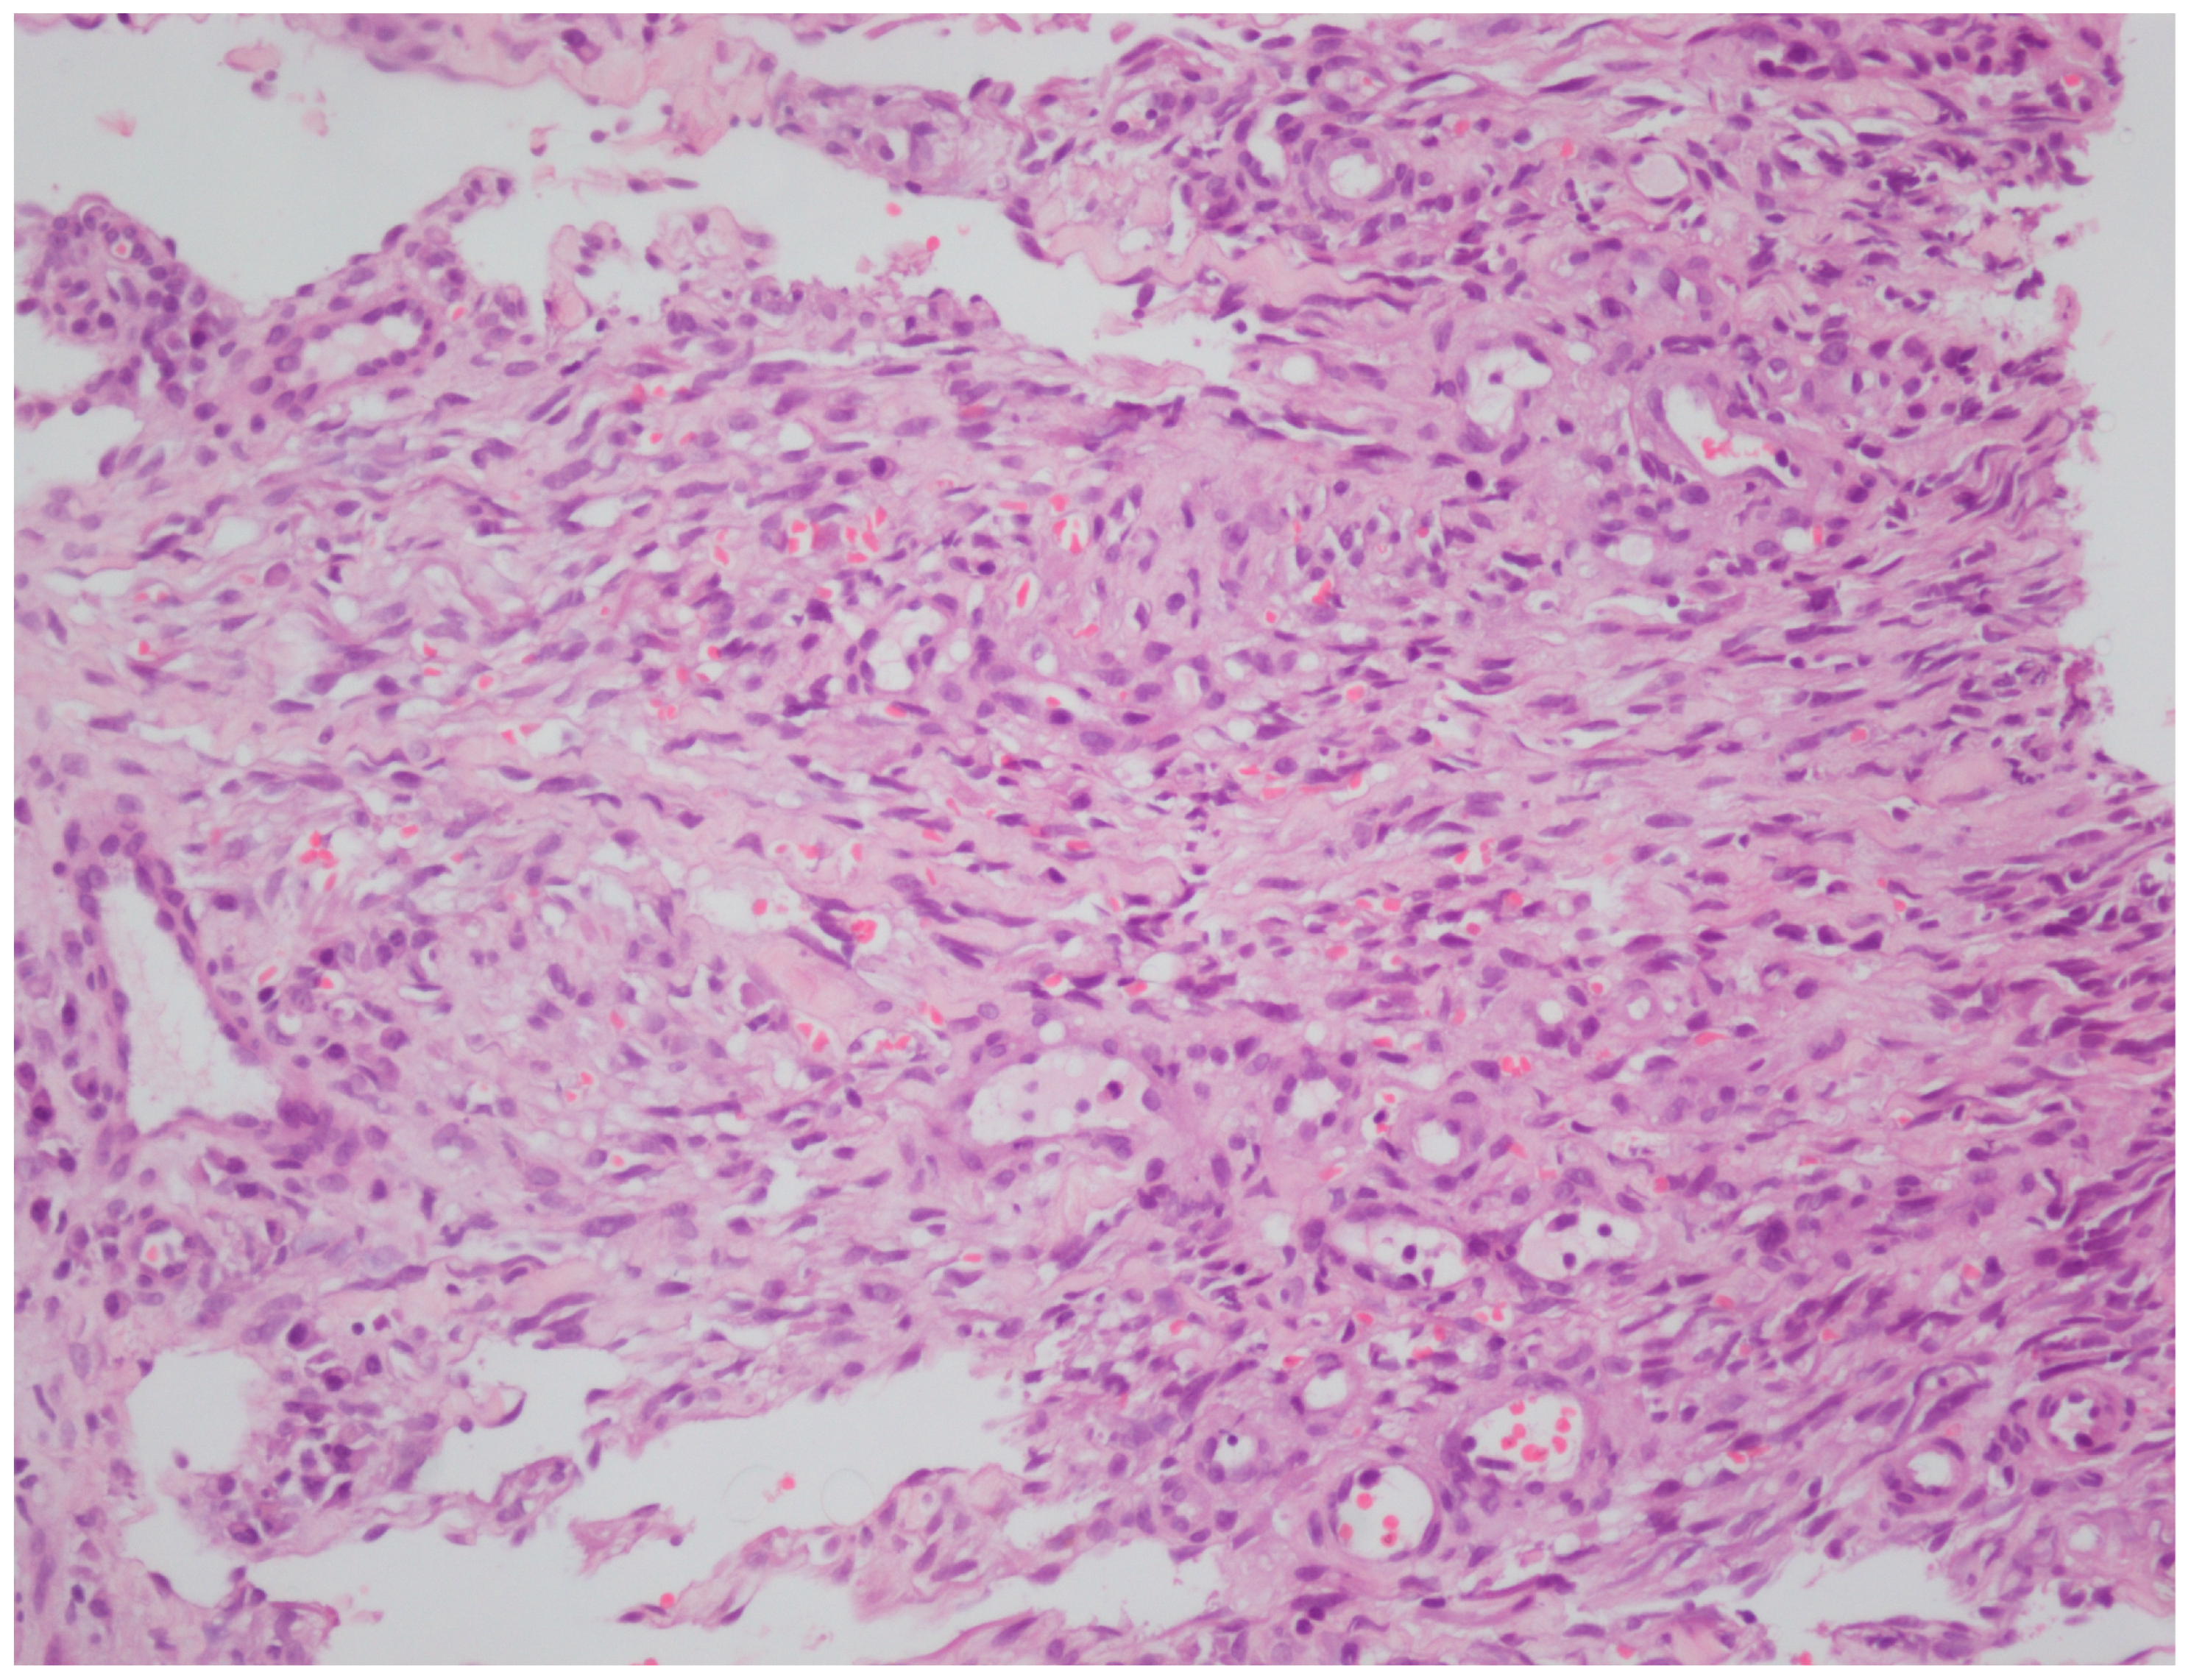

2.5. Histopathological Processing and Immunohistochemistry